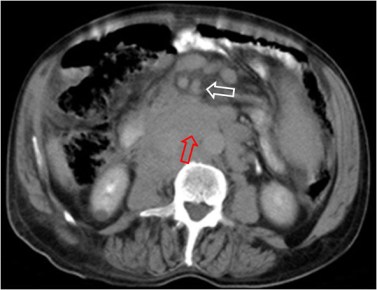

SIGNO DEL SANDWICH

Signo de linfoma abdominal tanto en la TC como en ecografía. Consiste en la presencia de masas adenopáticas que rodean y desplazan la arteria y la vena mesentéricas superiores sin comprimirlas.

La fotografía corresponde a un paciente con linfoma (flecha roja) que forma conglomerados adenopáticos que respetan los vasos mesentéricos (flecha blanca).

Por extensión, se puede emplear este signo en conglomerados linfomatosos que rodean pero respetan otras estructuras vasculares diferentes de los vasos mesentéricos, como vemos en el ejemplo siguiente con las arterias renales.